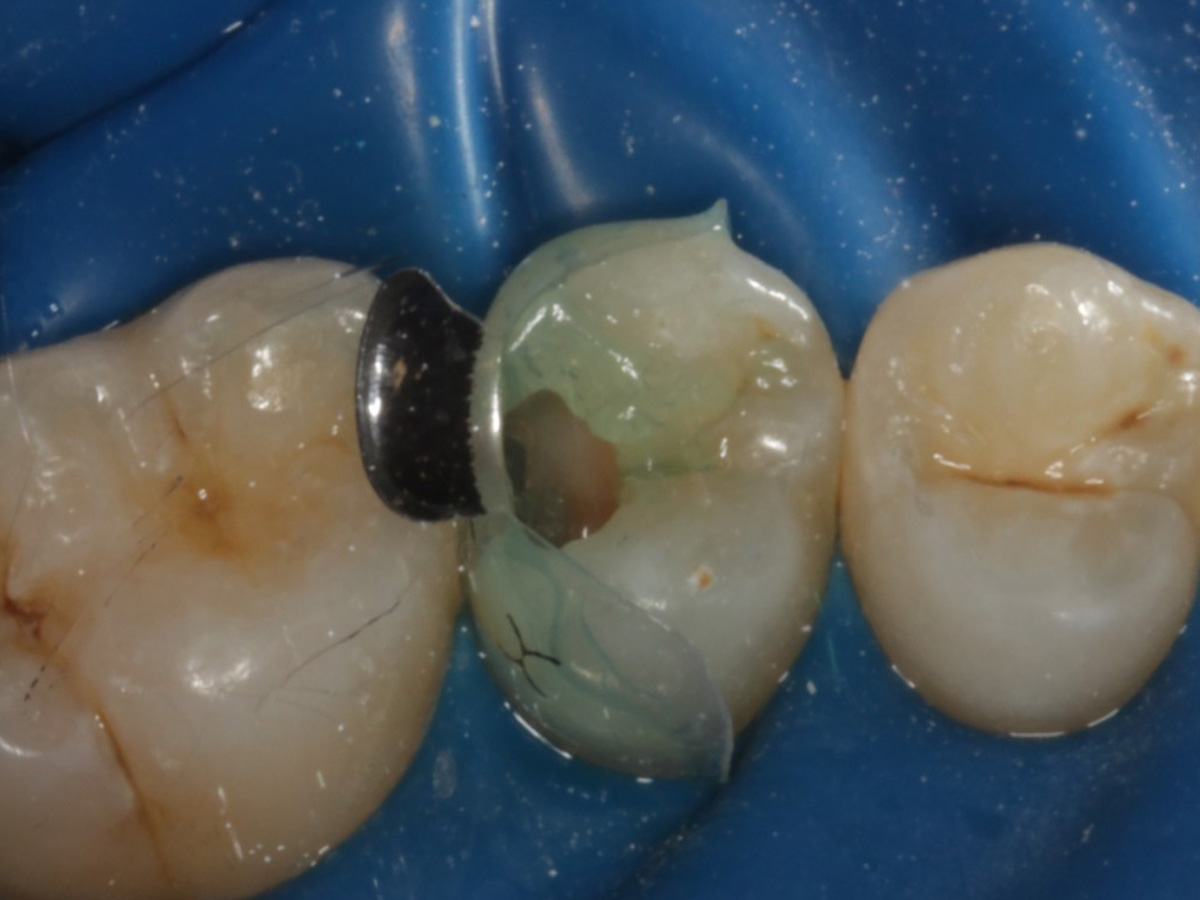

Abbildung 4

Schutz des Nachbarzahnes und des Kofferdams mit wiederverwandter Bioclear Biofit Matrize (gereinigt und sterilisiert); Separation zur Applikation der Matrize mit Heidemannspatel